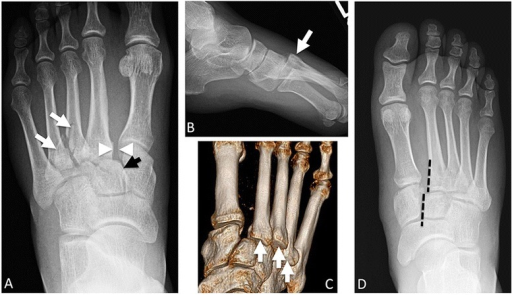

Weight-bearing AP radiograph of the foot demonstrating a Lisfranc injury. There is loss of alignment between the medial border of the 2nd metatarsal and the medial border of the middle cuneiform (disrupted 2nd TMT joint). There is widening between the 1st and 2nd metatarsal bases (>2mm). A fleck sign is visible at the base of the 2nd metatarsal representing an avulsion of the Lisfranc ligament.